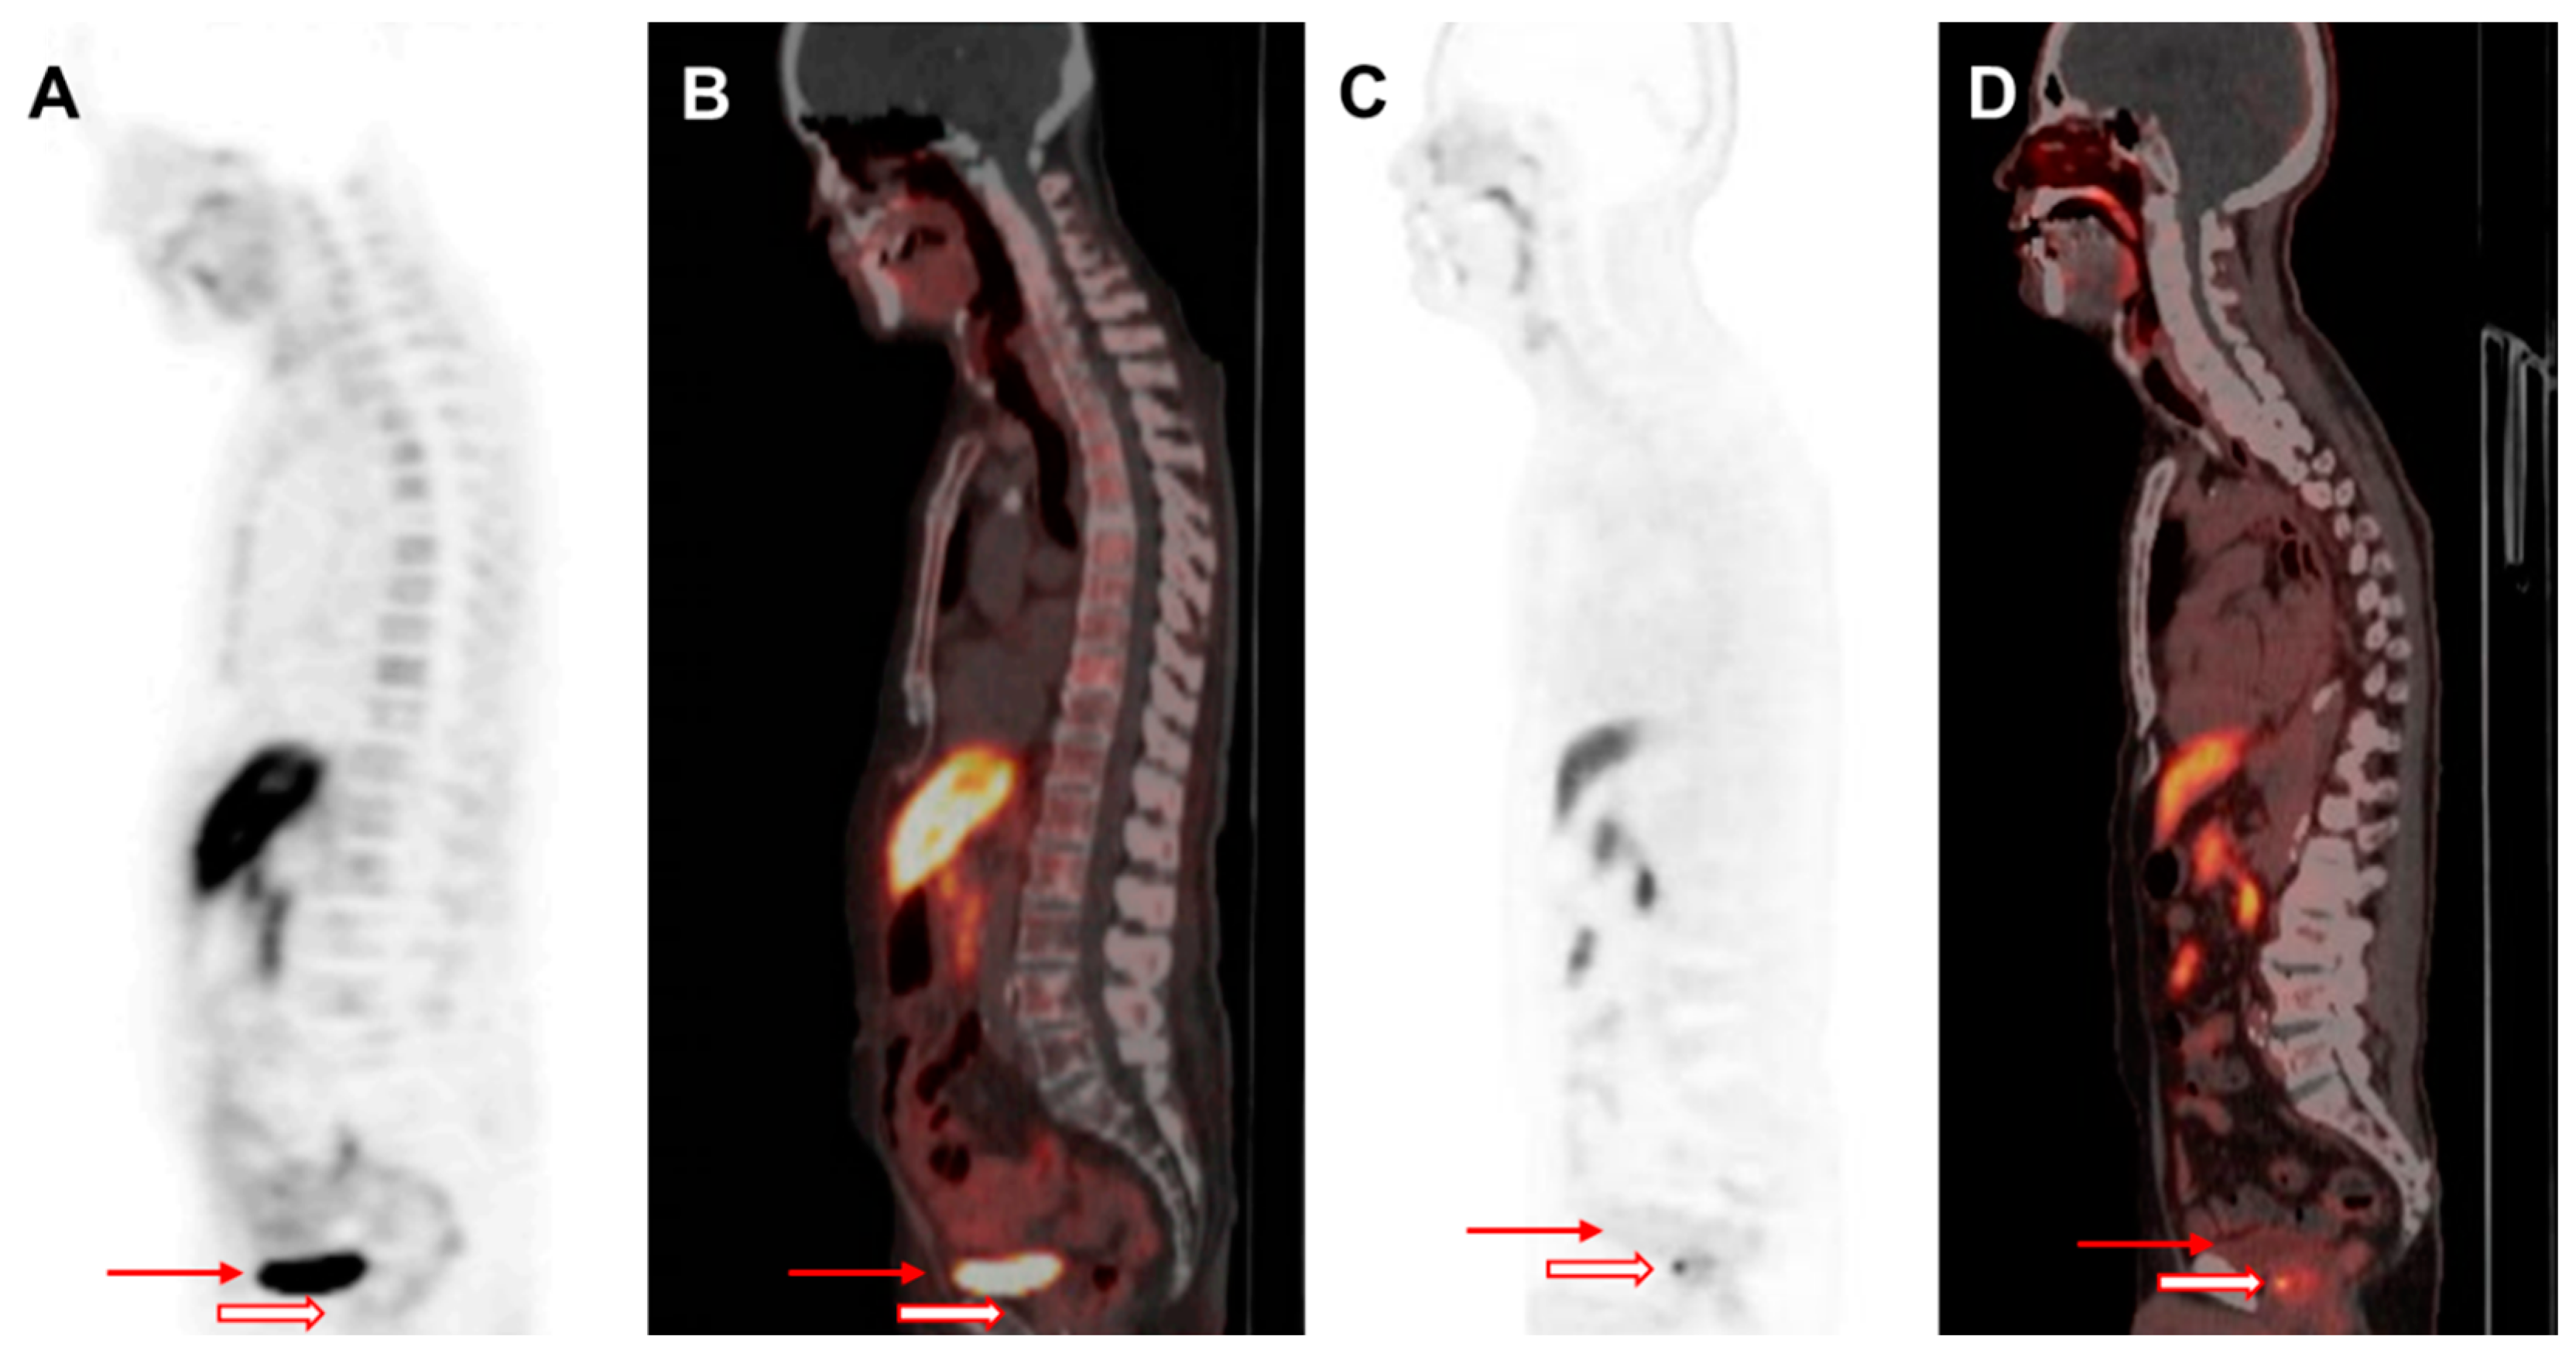

F-18-labeled radioligands have been investigated as alternatives to Ga-68-based agents, offering advantages, including greater availability and improved image resolution. F-18 DCFPyL has demonstrated a strong diagnostic performance in both the primary staging and restaging of PCa [52,53]. F-18 florastamin (F-18 FC303) is an emerging PSMA-targeted diagnostic radioligand that exhibits a higher tumor-to-background contrast as compared to F-18 DCFPyL, facilitating superior detection of osseous metastases, small metastatic lymph nodes, and primary tumors on delayed imaging [54]. Additionally, F-18 PSMA-1007 has been developed to minimize urinary excretion, enhancing the detection rates at lower PSA levels in both BCR and initial staging [42,55,56] (Figure 2). More recently, F-18 F-rhPSMA-7.3, which has received FDA approval, has been extensively evaluated and has demonstrated excellent diagnostic accuracy for nodal staging in intermediate- to high-risk PCa patients (Figure 3) [57].